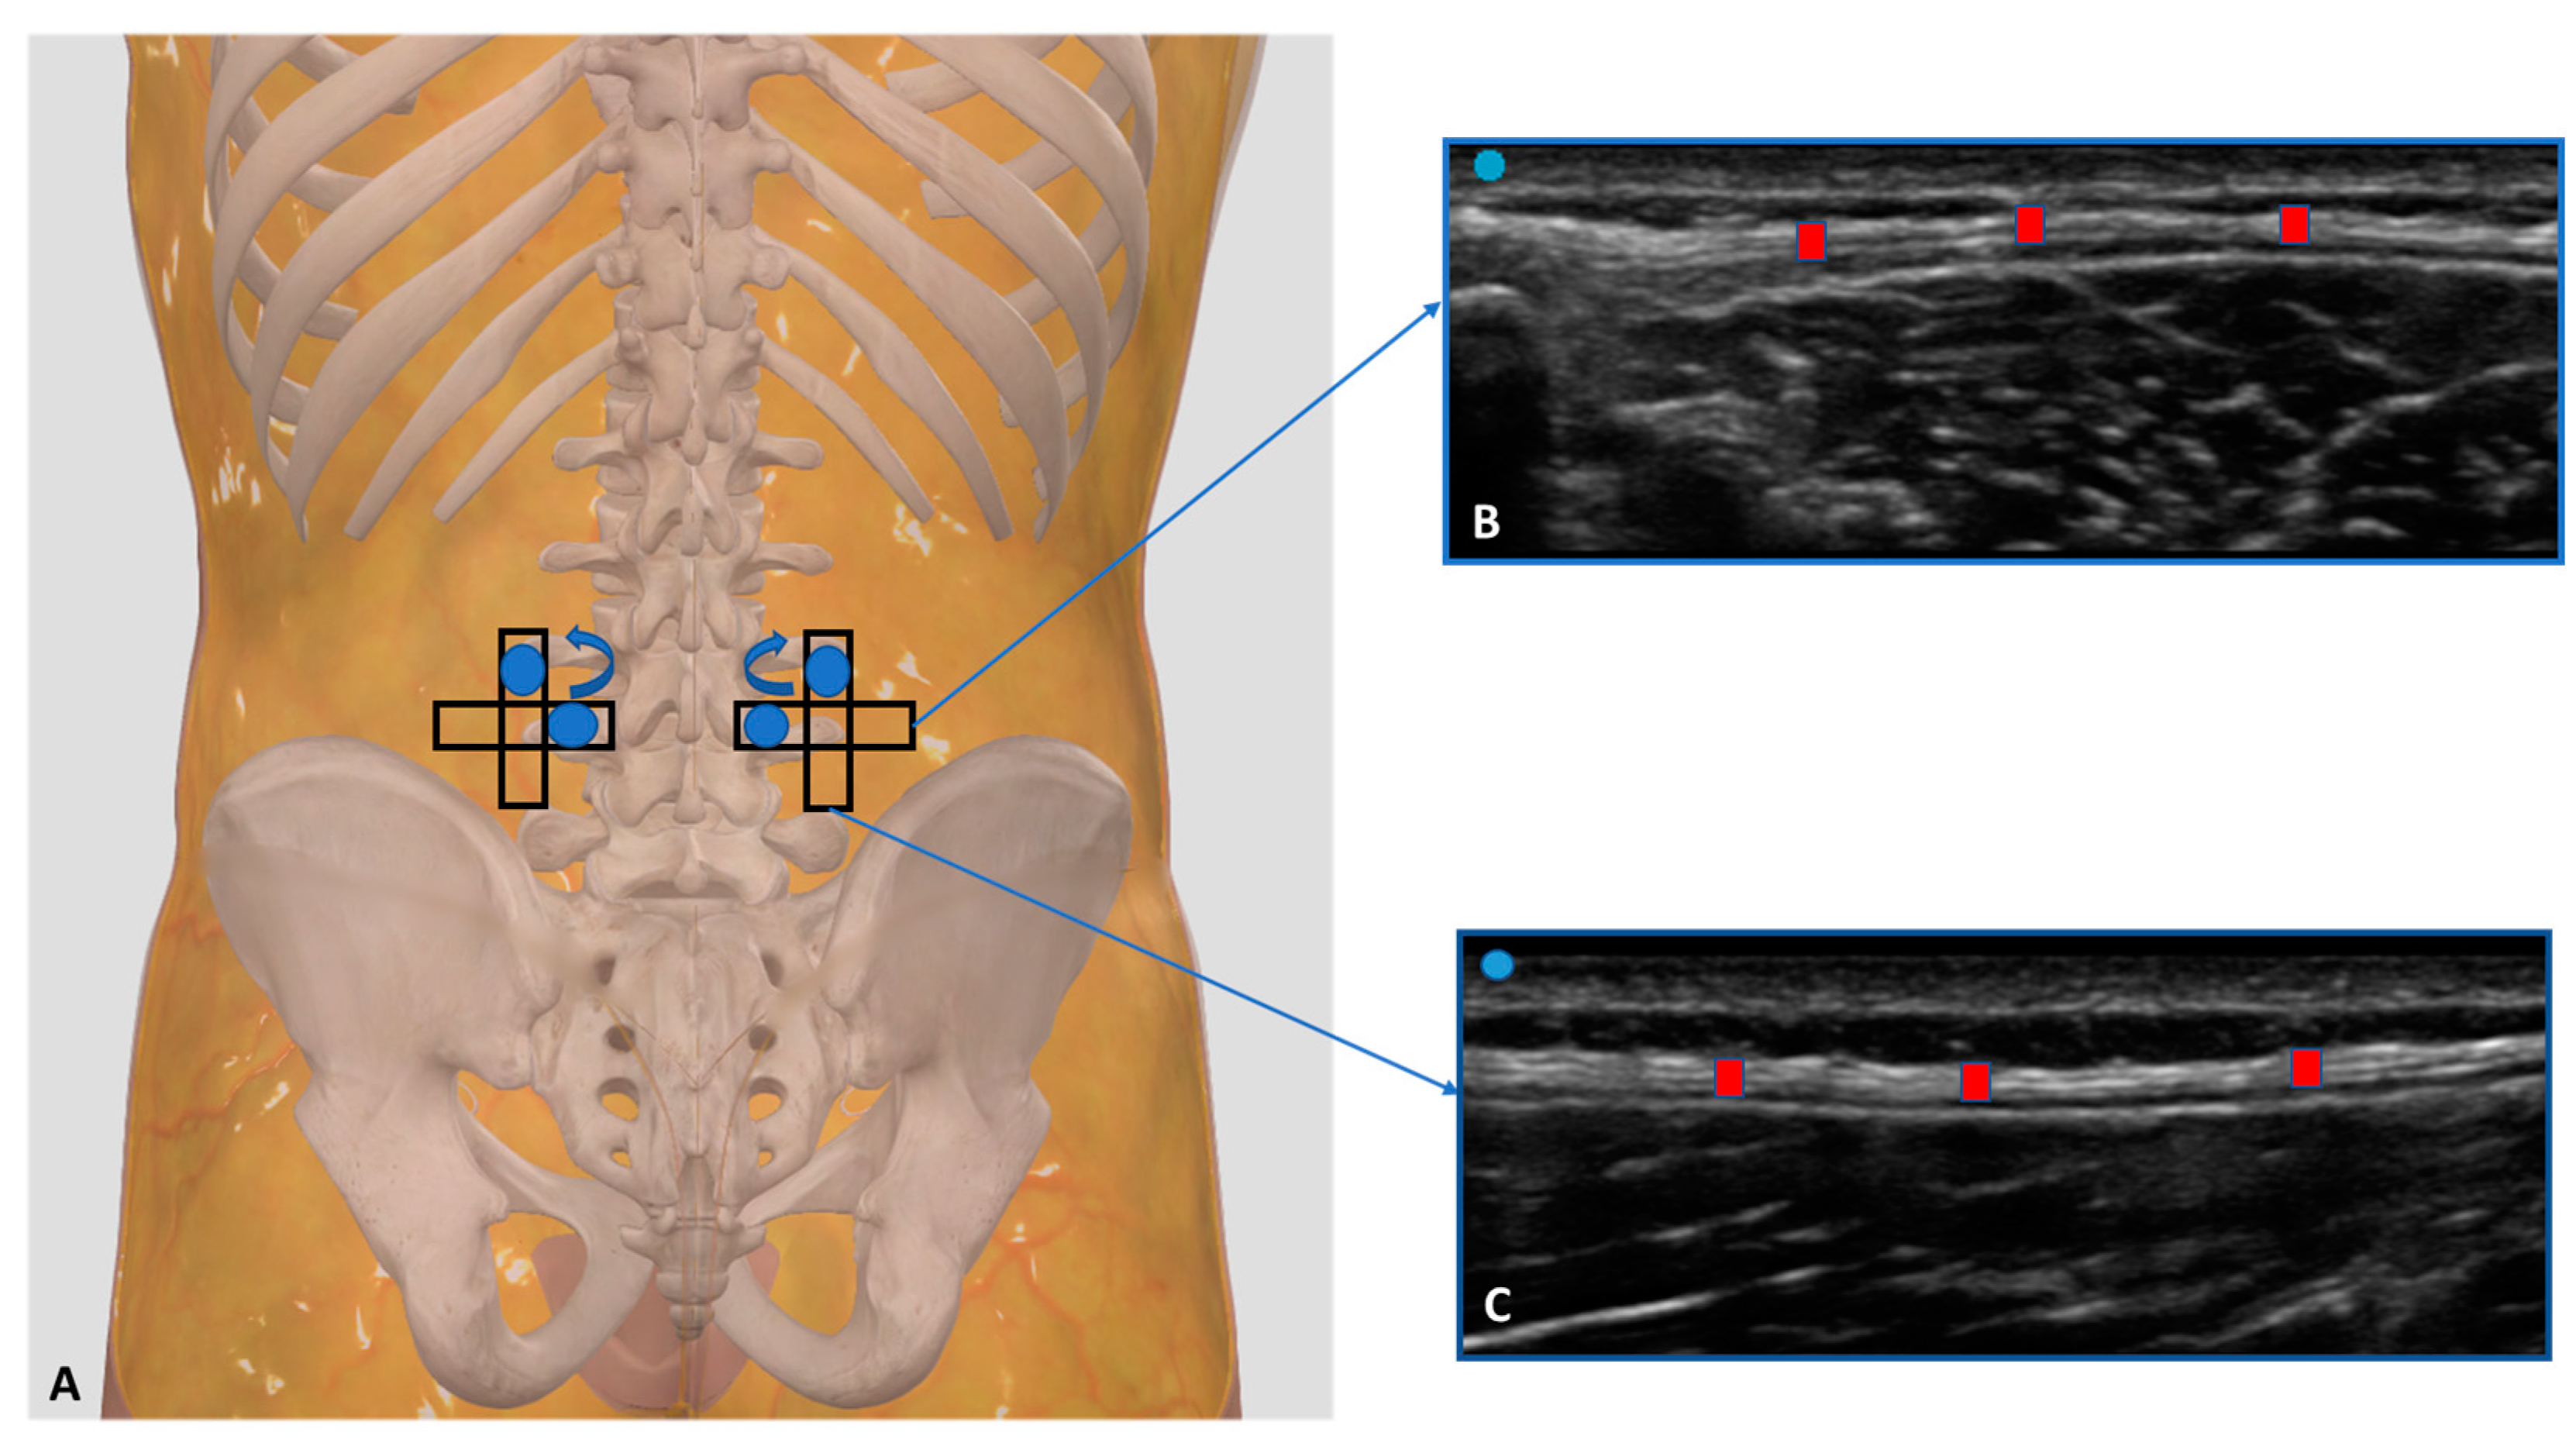

The ultrasonographer used the short axis beforehand, because it is the best axis to visualize and follow the landmarks correlated with the fascial layers’ visualization imaging used by Pirri et al. [25]; then, the probe was rotated 180° degrees to view at the same point in the longitudinal scan. A specific protocol was defined:

The L3 level of the lumbar spine: The patient was relaxed in the prone position and the US transducer was placed parallel to the spine, approximately 2–3 cm lateral to the L3 spinous process (Figure 1). The scans were taken on the short and long axis, rotating the transducer 180° degrees, paying close attention to maintaining the same structure in the center of the US monitoring image, and keeping the probe perpendicular.

Figure 1.

(A) Ultrasound measurements protocol of TLF thickness at the L3 level of the lumbar spine. Starting from the transversal axis to the long axis and rotating the probe 90° degree. Probe: black rectangle. (B) Transversal/short axis; (C) longitudinal/long axis. Red rectangle: TLF thickness.